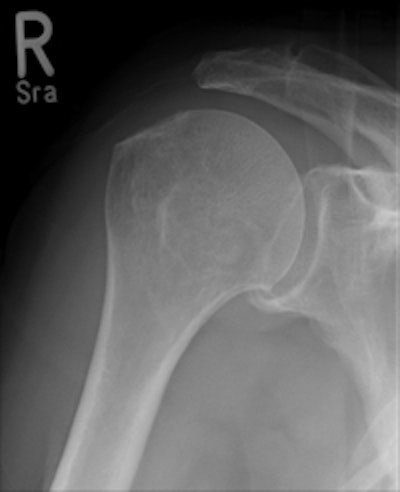

Data from 474 CR skeletal exams were collected; the CR cassette was then traded out for the wireless flat-panel DRX-1 detector to acquire an identical mix of 467 skeletal x-ray procedures. More than 50 patients were examined for each of nine types of inpatient and outpatient skeletal studies performed from January to June 2010.

Lehnert and colleagues also found that image quality also significantly improved in the shift from skeletal CR to DRX-1. Those results will be described in a separate study.